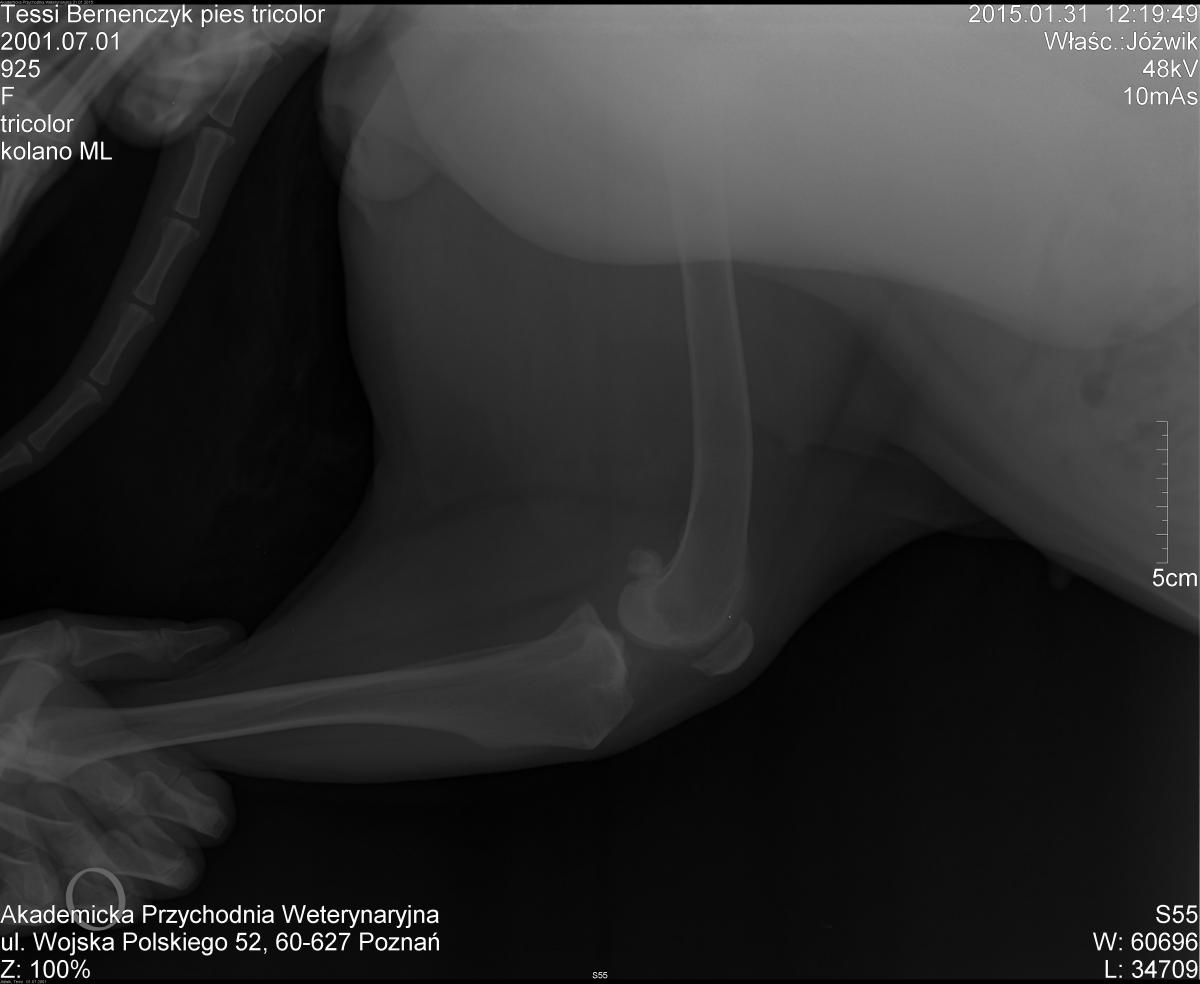

• Location

magda j

3. Tosia po wizycie u Bieżyńskiego, okazuje się że więzadło jest całe ale nadal nie wiemy skąd to klikanie w kolanku, bioderka również prześwietlone ma idealne. Jesteśmy w punkcie wyjścia. Co robić?